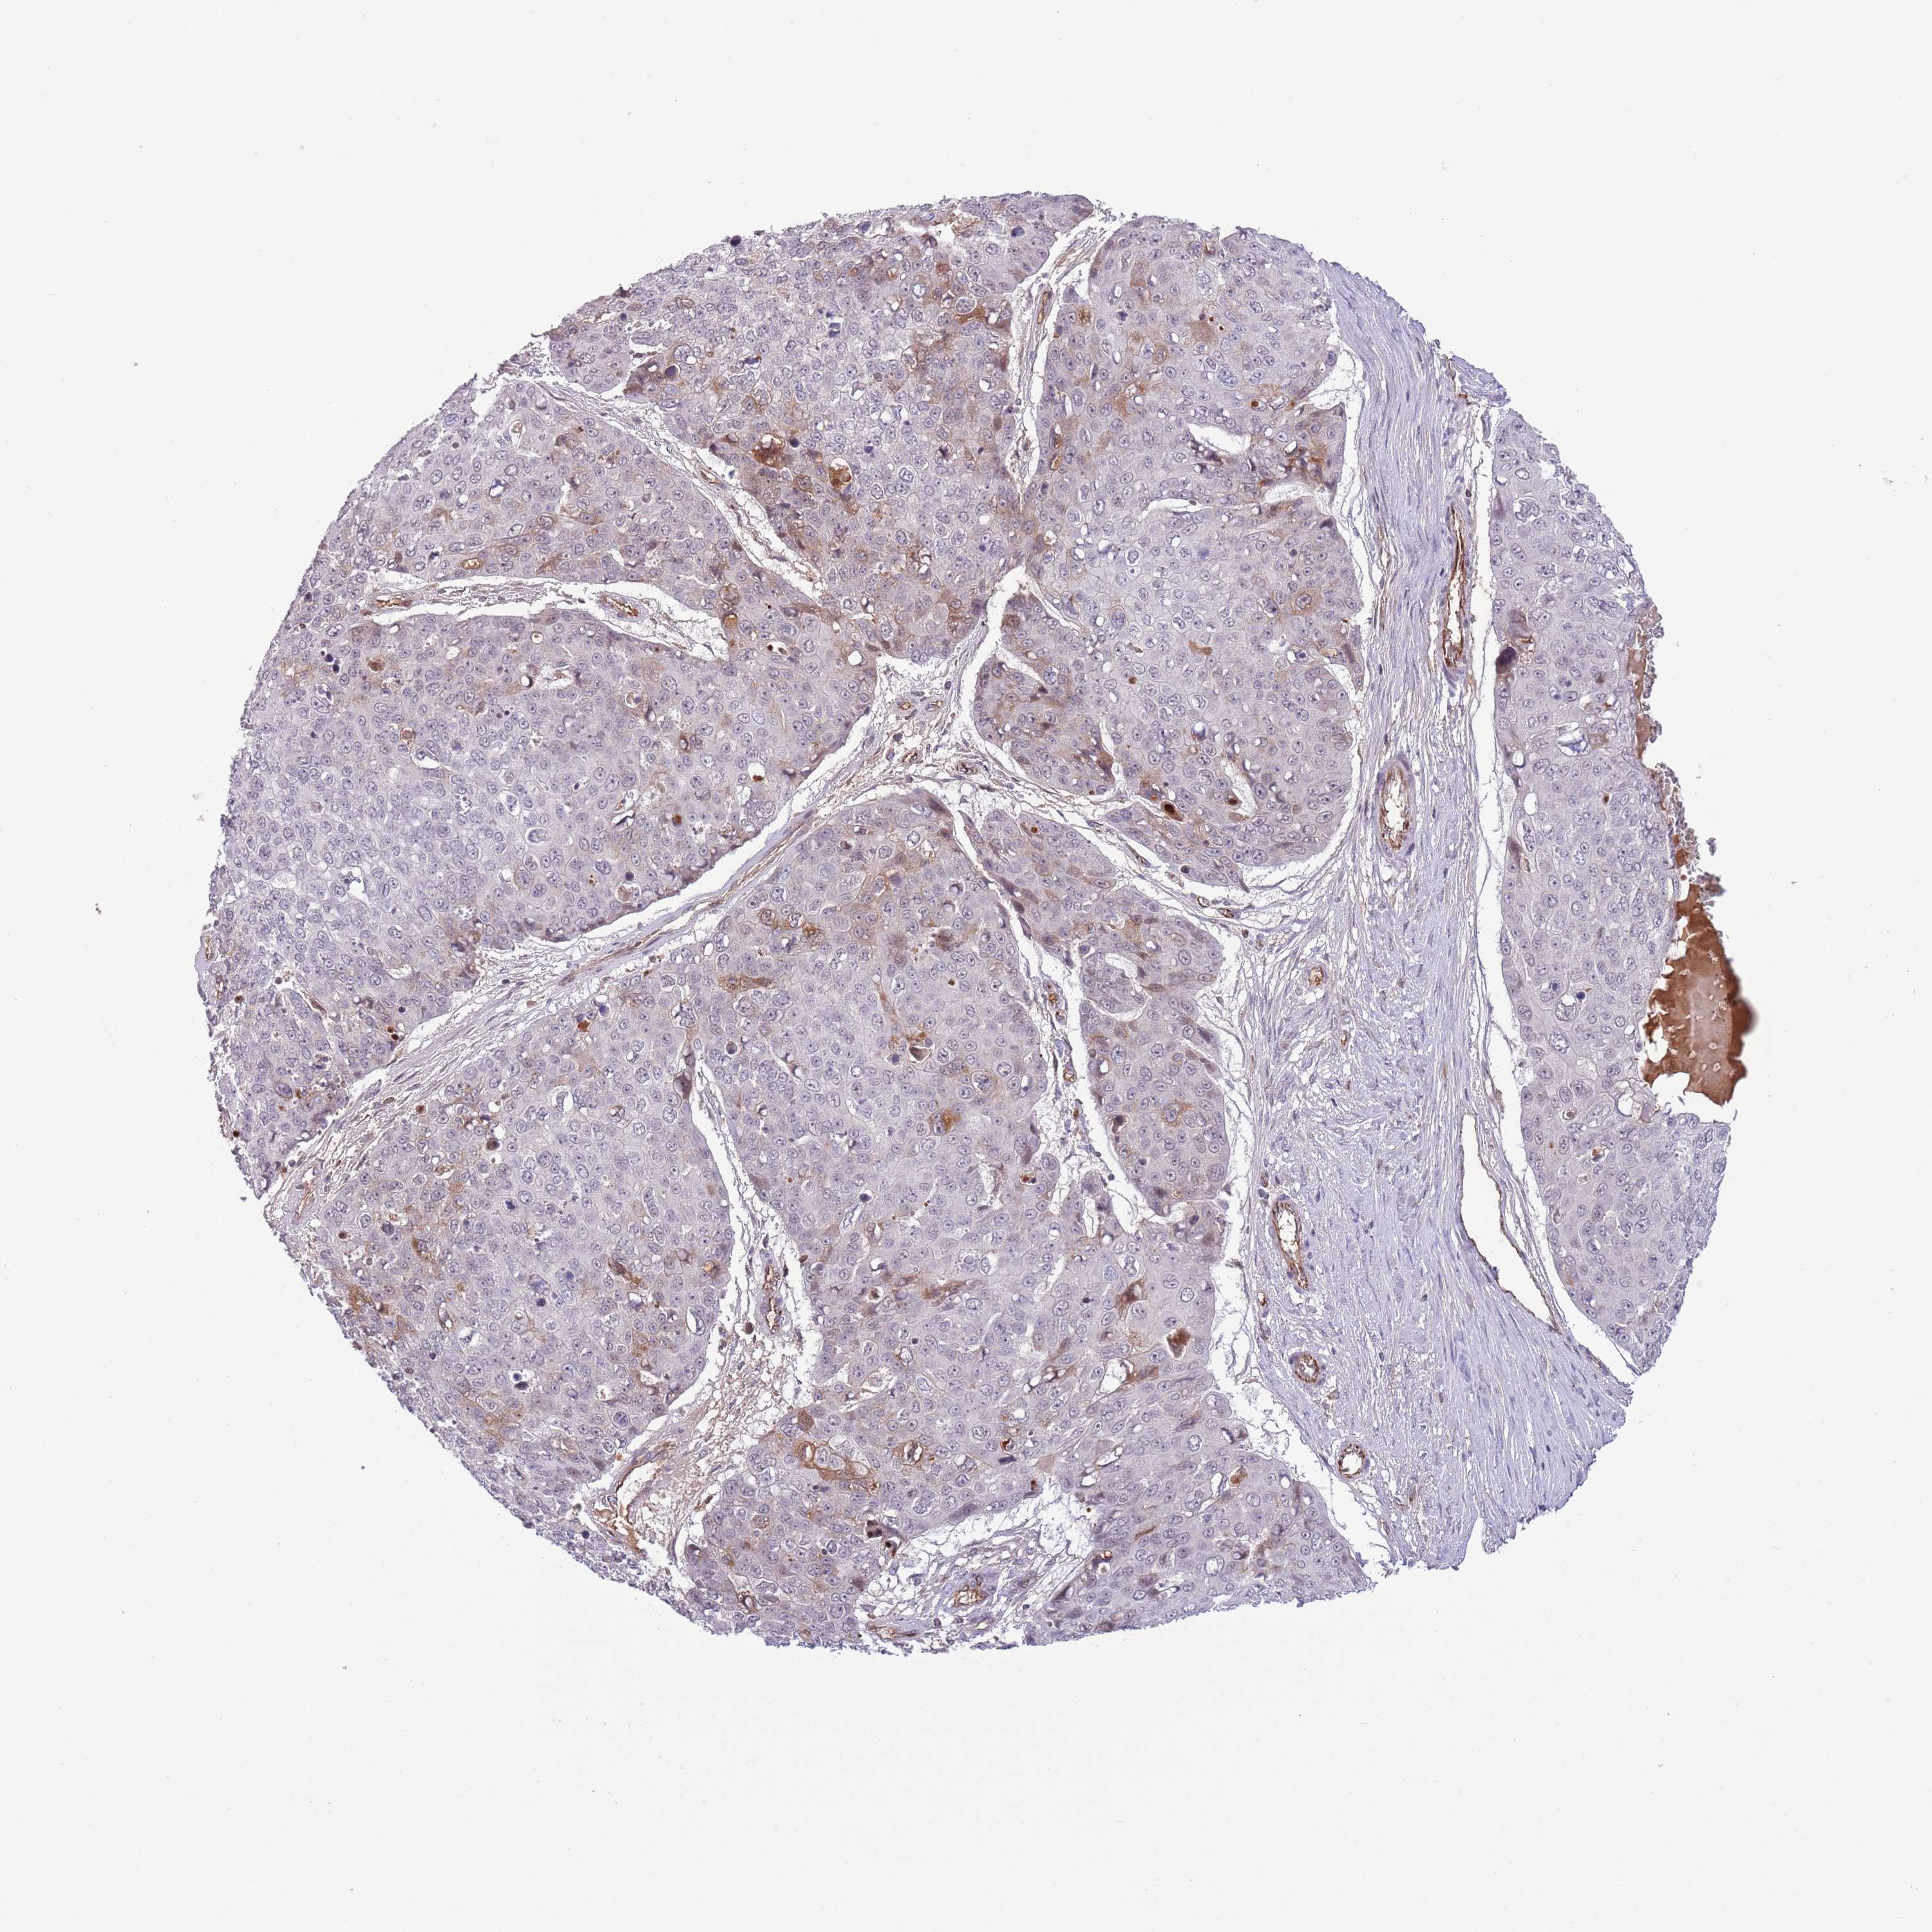

SKIN CANCER - Protein expressioni

A mouse-over function shows sample information and annotation data. Click on an image to view it in a full screen mode. Samples can be filtered based on level of antibody staining by selecting one or several of the following categories: high, medium, low and not detected. The assay and annotation is described here.

Antibody stainingi

Antibody staining in the annotated cell types in the current human tissue is reported as not detected, low, medium, or high, based on conventional immunohistochemistry profiling in selected tissues. This score is based on the combination of the staining intensity and fraction of stained cells.

Each image is clickable and will lead to virtual microscopy that enables deeper exploration of all samples and also displays staining intensity scores, fraction scores and subcellular localization as well as patient and tissue information for each sample.

Antibody HPA048767

Squamous cell carcinoma, NOS

Squamous cell carcinoma, metastatic, NOS